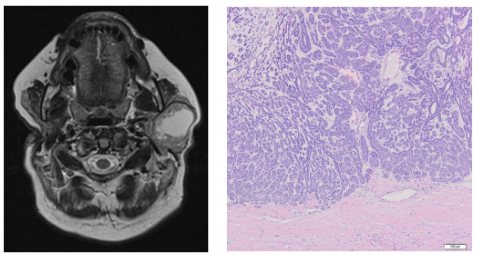

图4. 肿瘤被纤维包膜包围,没有侵袭的迹象,这是腺瘤的典型特征。该肿瘤显示基底细胞腺瘤的结构(膜状生长模式),基底样细胞的岛状结构,偶尔散布有空泡或小囊性间隙,细胞岛与间质明显区分(H&E染色,× 10)

组织病理学检查证实所有肿瘤均为基底细胞腺瘤(膜生长型)。肿瘤被纤维包膜包围,没有侵袭迹象。免疫表型模式如下:p63蛋白(+)、S-100蛋白(±)、上皮膜抗原(EMA)(+),CD117蛋白(±)、平滑肌肌动蛋白(SMA)(+)。肿瘤成功切除(图4)。